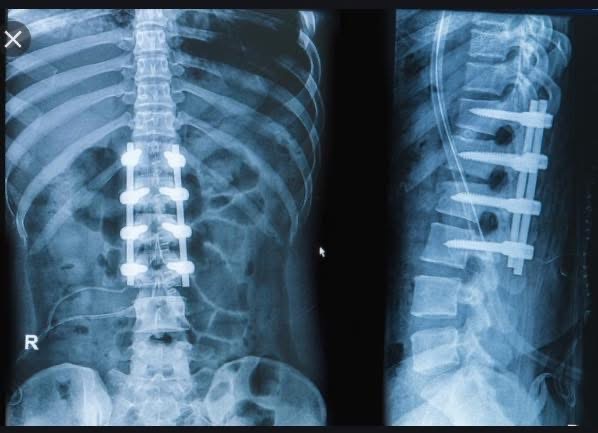

就在這個月,2025年十月十號,Tiger Woods再度上手術台。

這是他人生第七次背部手術。

這一次,美國脊椎名醫替他換上一顆人工椎間盤。

從2014年的第一次「小手術」到2025年的「人工置換」,這條脊椎走過了11年、七次手術,無數復健與止痛針。

2025年,這次是Disc Replacement(椎間盤置換)。